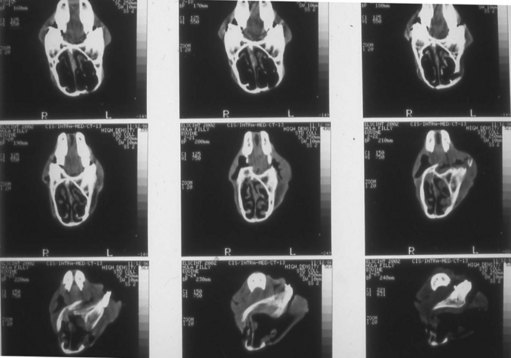

Foals should be evaluated carefully for aspiration pneumonia and to rule out associated congenital defects. The degree of the deformity can be determined by oral radiographic examination, and computed tomography of the skull might be useful to confirm the position and degree of premaxillary/maxillary deviation and nasal obstruction (Fig. 19.15). Dental impressions of the upper and lower arcades from the premolars to the incisors can help the surgeon determine the amount of space created on the concave side of the premaxillae/maxillae when the deformity is corrected and the upper and lower incisor arcades are brought into proper occlusion (Fig. 19.16). Occlusal abnormalities of the premolars causing wear should be corrected prior to surgery. This involves re-establishing a normal occlusal angle on the premolar arcades and leveling the incisors (Fig. 19.17).

image

Fig. 19.16 Plaster of Paris dental model of the upper arcade from a wry-nosed foal. The model has been cut and straightened to bring the upper and lower incisor arcade into proper occlusion. The white wedge indicates the angle of rostral and lateral displacement required to correct the deformity.